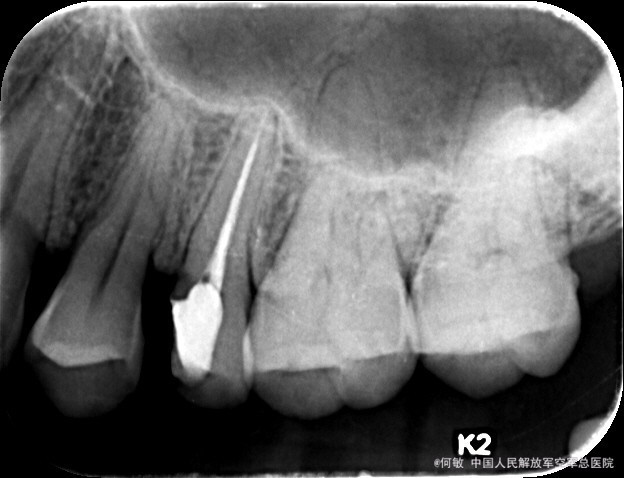

检查:25近中邻牙合面暂封完好,叩痛(-),牙体无松动,牙龈未见异常 X线示:25已根治,根充良好,根充物恰到根尖孔,根尖及牙周未见异常

诊断:25牙体缺损 治疗计划:25玻璃纤维桩+全冠冠修复 治疗:1.取局部印模,腭根根管桩道制备,置玻璃纤维桩,堆树脂核,固化,预备牙体,取模,比色:A3, 寄送加工厂,制备临时冠,试戴,调合,磨光,粘固临时冠 2.主诉:戴牙 检查:25临时冠完好,叩痛(—),牙体无松动,牙龈未见异常 处置:戴入25全冠,调节使就位顺利,与基牙密贴,冠边缘伸张合适,邻接恢复良好,调牙合,抛光,患者满意,玻璃离子水门汀粘固,嘱须知